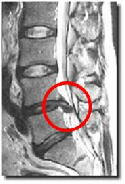

<腰椎椎間板ヘルニア>と腰痛

mriヘルニア 人間の背骨は24個の骨で構成されています。その骨と骨の間には椎間板と呼ばれるクッションがあります。椎間板は、繊維輪と髄核で構成されます。 繊維輪に亀裂が生じ髄核が繊維輪を破って飛び出た事を椎間板ヘルニア(uncontained type)と言います。飛び出した椎間板が神経などを圧迫する事により臀部・下肢の激しい痛みやシビレなどの症状を引き起こします。繊維輪を破らずに膨れたヘルニア(contained type)もあります。感覚障害、冷感、筋力の低下、排尿障害がある場合は速やかに病院受診が必要。

uncontained typeは痛みが劇的だが治癒まで比較的早い傾向。

contained typeは痛みが中程度だが長引きやすい傾向。